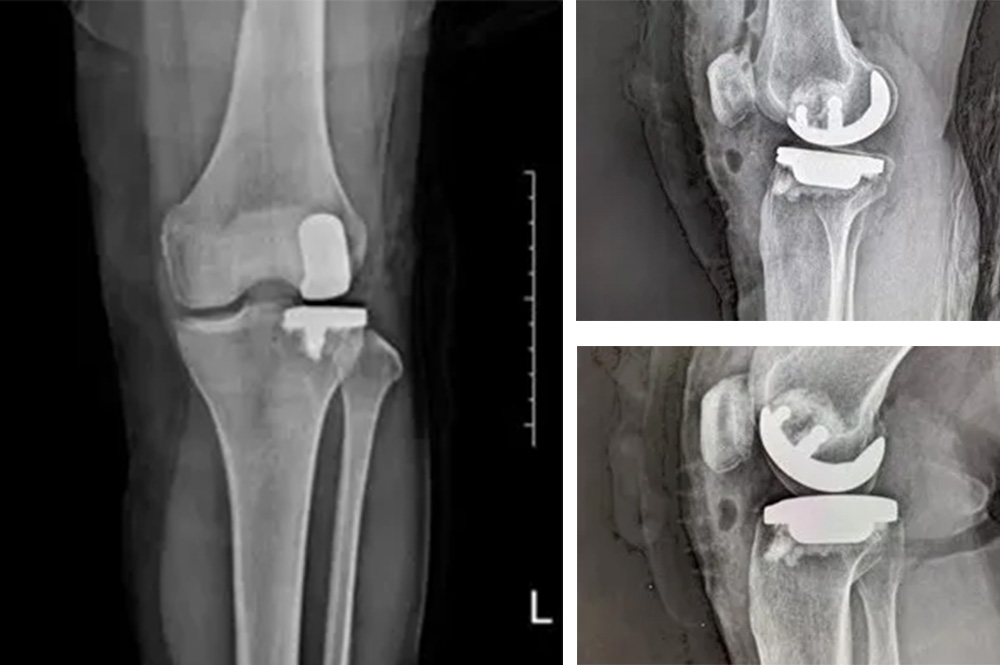

“傳統(tǒng)全膝關(guān)節(jié)置換會(huì)切除所有關(guān)節(jié)面,而單髁置換只替換病變的部分,保留了健康的韌帶和軟骨,更符合‘精準(zhǔn)醫(yī)療’理念。”羅醫(yī)生說(shuō)。

經(jīng)過(guò)詳細(xì)的體格檢查、影像學(xué)評(píng)估和三維重建,醫(yī)療團(tuán)隊(duì)確認(rèn)鮑奶奶的情況非常適合進(jìn)行膝外側(cè)單髁置換術(shù)。這種微創(chuàng)手術(shù)創(chuàng)傷小、恢復(fù)快,能夠最大程度保留膝關(guān)節(jié)的自然結(jié)構(gòu)和功能。

手術(shù)當(dāng)天,骨科團(tuán)隊(duì)采用微創(chuàng)切口,僅約8厘米,遠(yuǎn)小于傳統(tǒng)全膝關(guān)節(jié)置換手術(shù)切口。術(shù)中精準(zhǔn)定位,僅置換病變的膝關(guān)節(jié)外側(cè)間室。

手術(shù)使用了最新的單髁假體系統(tǒng),這種假體設(shè)計(jì)更符合人體工程學(xué),能夠更好地恢復(fù)膝關(guān)節(jié)的自然運(yùn)動(dòng)軌跡。

“與傳統(tǒng)手術(shù)相比,單髁置換出血少,軟組織損傷小,術(shù)后疼痛輕。最重要的是保留了膝關(guān)節(jié)前后交叉韌帶和本體感覺(jué),患者術(shù)后感覺(jué)更像自己的‘原裝’膝蓋。”

膝外側(cè)單髁置換術(shù)是膝關(guān)節(jié)置換領(lǐng)域的重要進(jìn)展。與全膝關(guān)節(jié)置換相比,它具有明顯優(yōu)勢(shì):手術(shù)創(chuàng)傷小,僅置換病變部分;保留更多自然結(jié)構(gòu)和韌帶;術(shù)后恢復(fù)快,住院時(shí)間短;術(shù)后膝關(guān)節(jié)感覺(jué)更自然,活動(dòng)度更好。